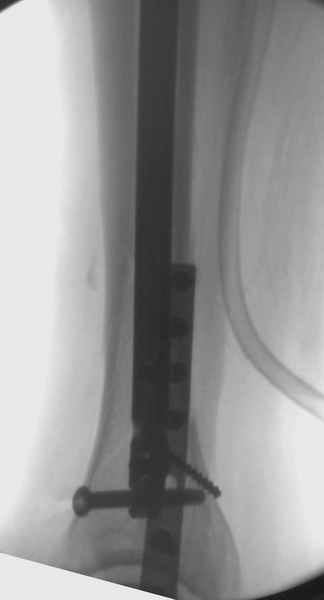

Повреждение такой локализации, на которой применимы и аппарат (классический Илизарова или гибридный), пластина, особенно Locked Plate, и гвоздь с блокированием. В нашей клинике был бы выполнен закрытый интрамедуллярный остеосинтез. Желательно использовать гвоздь с возможностью провести более чем 2 обычных фронтальных винта в дистальном отломке.

Здесь мы использовали новый Synthes Nail с дополнительными дырками, в проксимальной части 4: по две косых и поперечные (один стандартный а другой динамический), в дистальной части две поперечные, прямая и косая. Вес больного более 120 кг, нагрузку начнем через месяц.

Получилось красиво, поздравляю. Вверху можно было ограничиться одним винтом во фронтальное статическое отверстие, зачем два 45-градусных?

При такий спирали задний край tibia может быть сломан - нет ли этого в данном случае? На всякий случай можно было ввести 1-2 винта 4,5 мм спереди назад мимо гвоздя. Хотя самый дистальный блокирующий винт, возможно, зацепил этот отломок. А какой тут диаметр гвоздя и locking винтов?